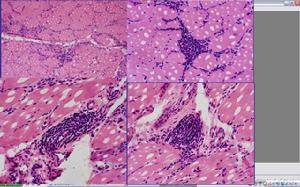

2.實驗室檢查,血清攝 131I率、T3和T4值高於正常;血、尿中肌酸增高;肌電圖顯示為非特異性肌病圖;肌活檢符合肌源性疾病。